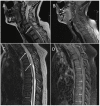

Figure 1. Sagittal MRI images from case one

(A) T2 sequence of the patient's cervical spine showing intradural hematoma (white arrow); (B) Post-contrast T1 sequence of the patient's cervical spine showing no abnormal enhancement; (C) T2 sequence of the patient's thoracic spine showing the intradural hematoma (white arrows); (D) Post-contrast T1 sequence of the patient's thoracic spine showing no abnormal enhancement.